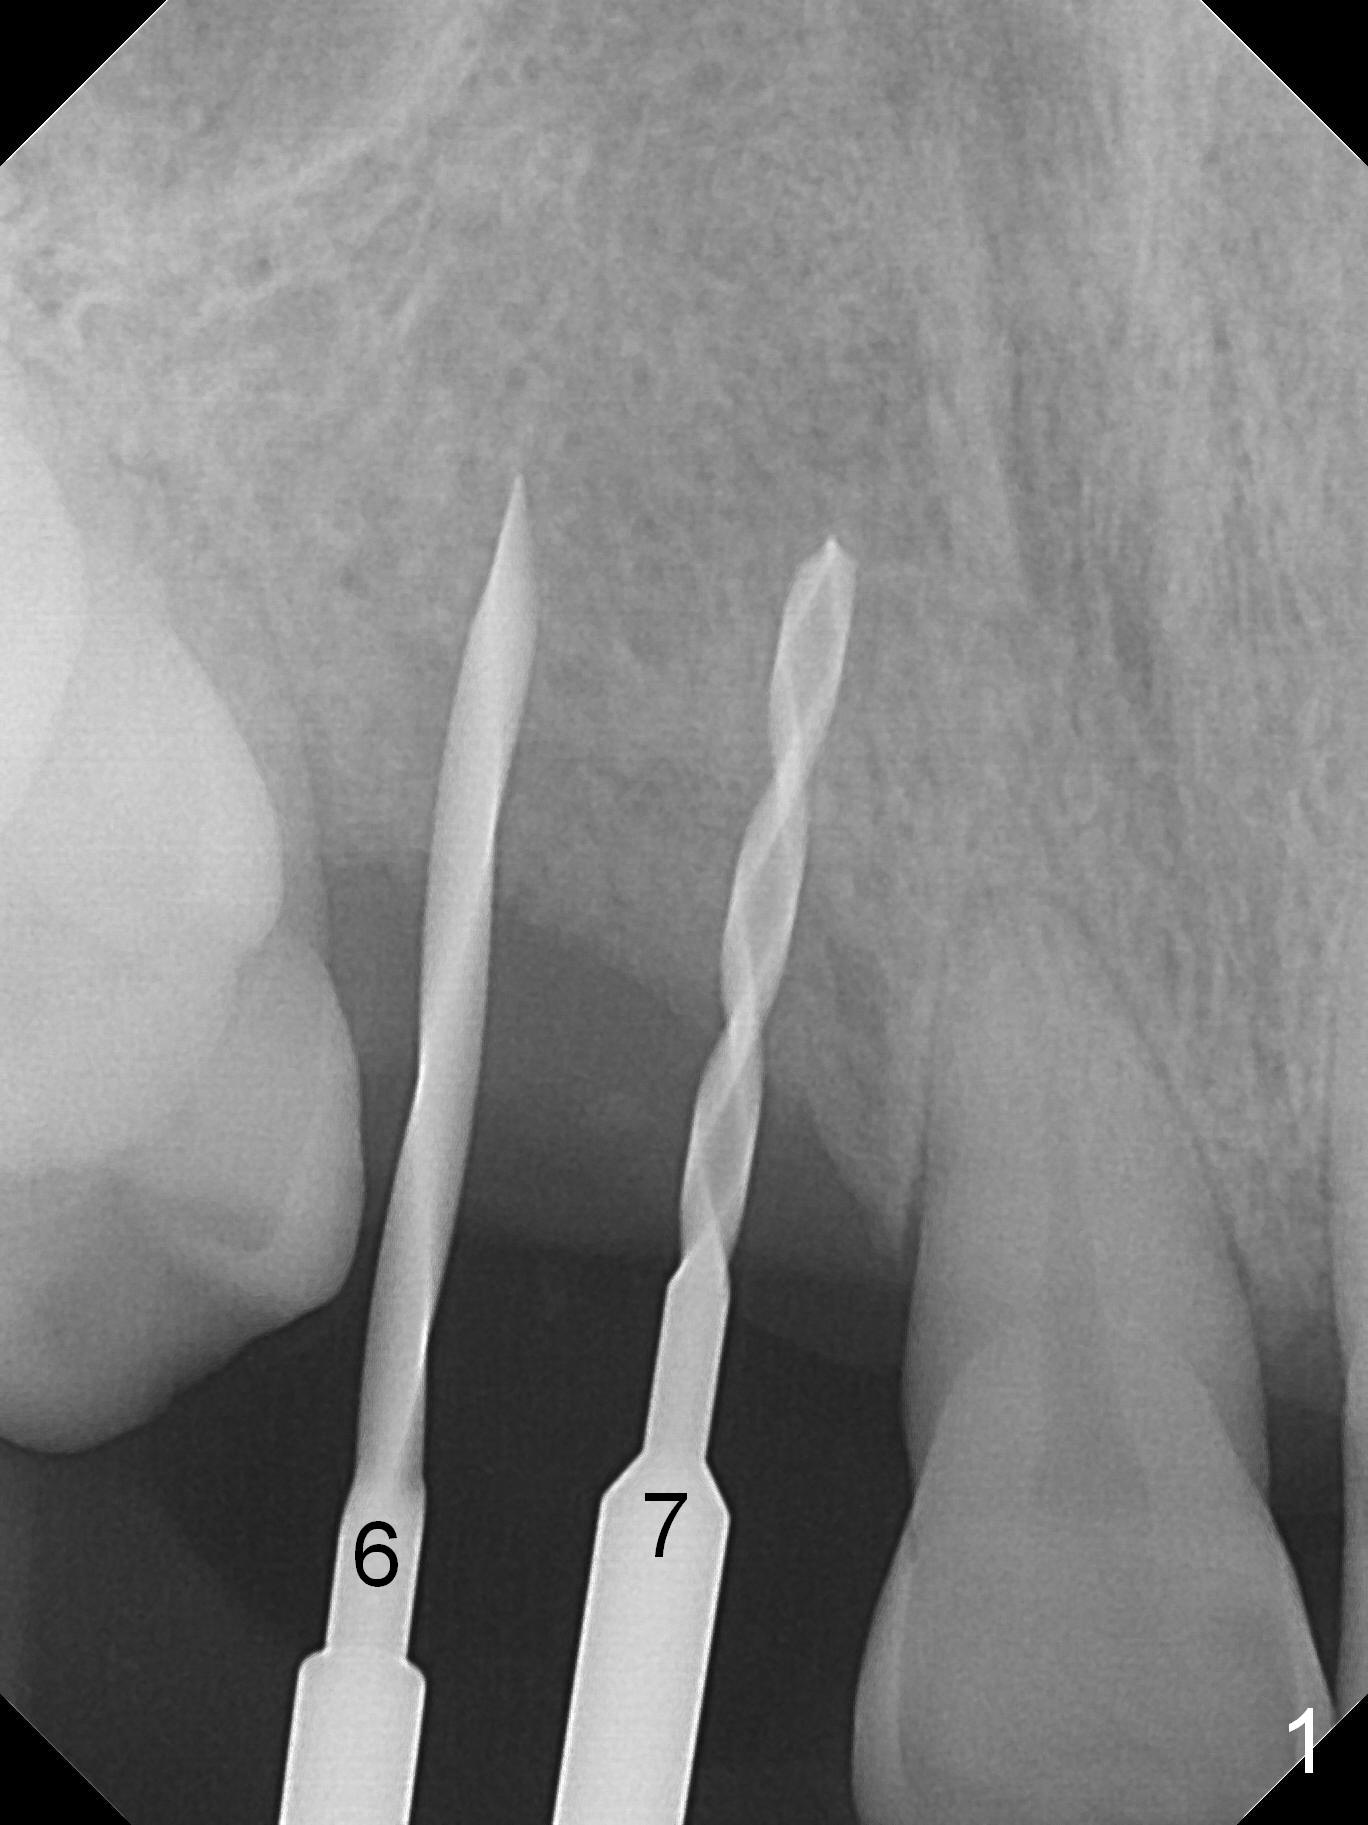

The ridge at the sites of #6 and 7 looks wide, but the bone is narrow (~ 4 mm) when the flaps are raised. Two of 3 mm 1-piece implants (3x16(2) and 3x14(4) mm) are placed (Fig.1,2). The other advantage of use of 1-piece implants is the narrow mesiodistal space. In fact the gingiva is wide and thick (4 mm). It is ideal to place implants with 4 mm cuff; unfortunately there is no 3x16(4) mm implant available at the site of #6. After adjustment of the abutment at #7, a splinted provisional is fabricated. Due to the shortness of the abutment at #6, definitive crowns may have to be splinted. Water Pik has been recommended.